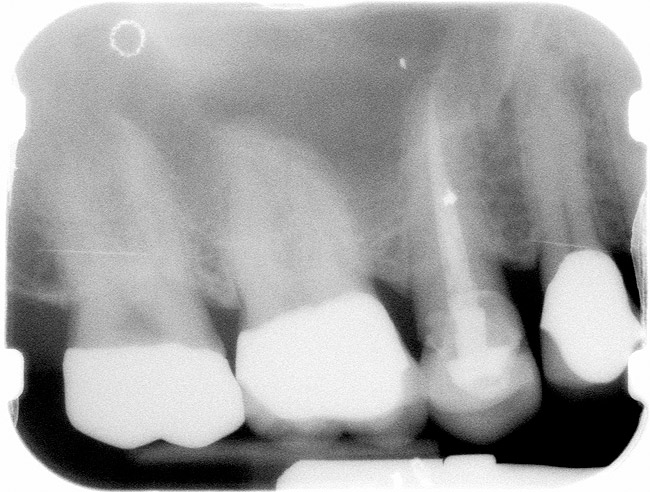

Figure 6  Endodontically treated maxillary right second molar.

Figure 6

Figure 7  Second molar with the palatal canal prepared for post placement.

Figure 7

Case 2

A Class IIIN maxillary left second molar required restoration (Figure 6). Four canals, a chamber space, and little cross section of tooth structure were in the gingival third. Gutta-percha was removed with a Peeso reamer supplied in the C-1 kit. The canal was shaped with a bur in the kit, which was the same size as the corresponding post (Figure 7). The tooth structure was bonded with Brush & Bond™ (Parkell, www.parkell.com), and then the resin cement was spun into the canal with a lenticulo spiral. A C-1 white post was placed in the palatal canals (Figure 8). The C-1 White Post is a fiber-reinforced composite post, which flexes at the same rate as dentin to minimize root stresses.